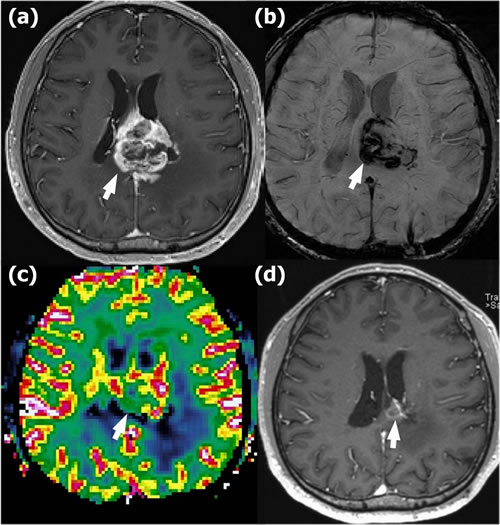

Figure 5: Radionecrosis in a 41-year-old man with glioblastoma in the left mid corpus callosum who underwent gross total resection and concomitant chemoradiotherapy (CCRT). a. Contrast-enhanced T1-weighted (CET1) magnetic resonance (MR) image obtained 18 months after CCRT completion shows newly appearing enhancing lesions in the left mid corpus callosum (arrow). b. Susceptibility-weighted imaging demonstrates significant dark areas in the corresponding enhancing lesions (arrow); the proportion of dark signal intensity (proSWMRI) was 40.5 %. c. The normalized relative cerebral blood volume map (nCBV) from dynamic susceptibility contrast perfusion-weighted imaging shows increased blood flow in the corresponding enhancing area (arrow) (calculated 90th percentile points in the cumulative nCBV histogram (nCBV90) = 2.84). d. Follow-up CET1 MR image obtained 36 months after the first appearance of the enhancing lesion shows an interval decrease in the extent of the enhancing lesion (arrow), suggesting radionecrosis.